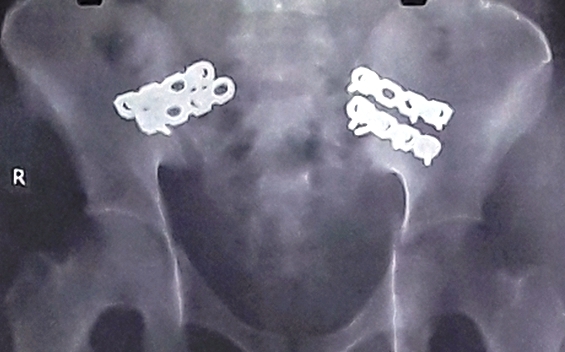

Bệnh nhân nhập viện được chỉ định xét nghiệp, chụp X-quang và chụp MRI. Kết quả, nạn nhân bị gãy xương chậu, thủng tạng rỗng, chảy máu nhiều cơ quan, tính mạng thanh niên rơi vào nguy kịch vì mất nhiều máu.

Khung chậu bệnh nhân được cố định qua ảnh chụp X-quang

Vừa xong thì bác sĩ của Bệnh viện Chấn thương Chỉnh hình tiếp tục thực hiện cố định khung chậu bị gãy, kiểm soát sốc… cho bệnh nhân.

Qua 3 giờ phẫu thuật, bệnh nhân được truyền 4 lít máu, huyết áp ổn định, da hồng hào trở lại. Các bác sĩ đã thở phào khi đã giữ lại tính mạng. Hiện, anh H. được theo dõi chờ tiếp tục mổ xử lý xương chậu, đóng hậu nhân tạo và điều trị tập vật lý trị liệu để đi lại bình thường.